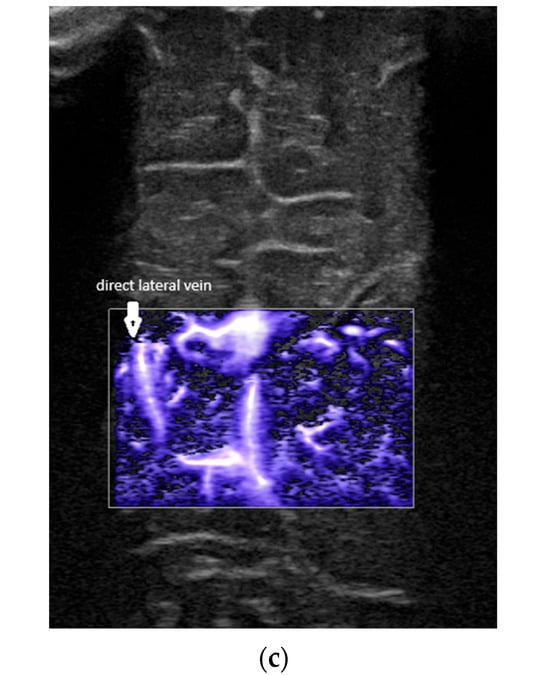

- Confluence posterior to the foramen of Monro, the most frequent variant (Figure 1).

- Confluence at the level of the foramen of Monro (Figure 2).

- A lack of identification of the confluence—wherein the terminal vein was absent on one or both sides—an example is the case presented in Figure 3, where the terminal vein was most probably draining in a direct lateral vein on the left side.